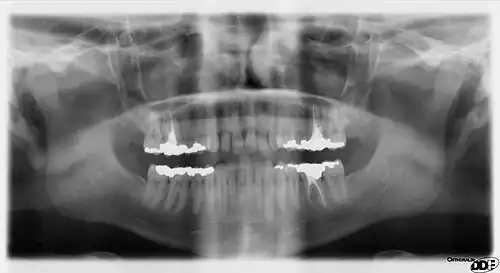

Panoramic films

A panoramic film, able to show a greater field of view, including the heads and necks of the mandibular condyles, the coronoid processes of the mandible, as well as the nasal cavity and the maxillary sinuses.

Panoramic X-ray radiography of the teeth of a 64-year-old male shows dental work performed mostly in UK/Europe in last half of 20th century

Panoramic films are extraoral films, in which the film is exposed while outside the patient's mouth, and they were developed by the United States Army as a quick way to get an overall view of a soldier's oral health. Exposing eighteen films per soldier was very time consuming, and it was felt that a single panoramic film could speed up the process of examining and assessing the dental health of the soldiers; as soldiers with toothache were incapacitated from duty. It was later discovered that while panoramic films can prove very useful in detecting and localizing mandibular fractures and other pathologic entities of the mandible, they were not very good at assessing periodontal bone loss or tooth decay.[18]